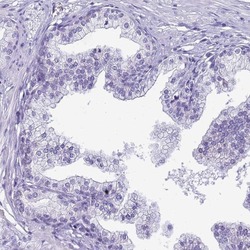

Immunohistochemistry

PA5-61223 IHC

Method:

Other validation